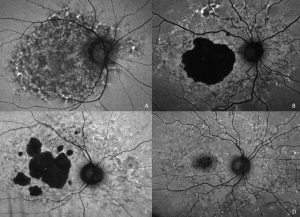

Characteristic features of PPS maculopathy were defined in one study as the following: “(1) bilateral pathology centered on the fovea; (2) fundus photography revealing paracentral macular hyperpigmented spots, pale yellow deposits, and/or patchy retinal pigment epithelium atrophy; (3) a dense array of hyper- and hypoautofluorescent spots and reticular fundus autofluorescence imaging abnormalities; and (4) foci of nodular retinal pigment epithelium enlargement on OCT imaging corresponding to hyperreflectance on near infrared reflectance imaging.”[8]

Fundus photography, fundus autofluorescence imaging (FAF), optical coherence tomography (OCT), and near-infrared reflectance imaging (NIR) are useful imaging modalities to establish a diagnosis of PPS maculopathy. Imaging findings are typically symmetric between both eyes, with rare cases of disease asymmetry.[11][12][21]

Color fundus photography typically shows more subtle manifestations compared to FAF. Hyperpigmented macular spots and deep yellowish subretinal deposits may be apparent, particularly in milder cases.[11][12][15][16] Patchy parafoveal RPE atrophy manifests in more advanced cases.[7][11][12][31]

Fundus autofluorescence imaging reveals a striking, densely packed array of hyper- and hypoautofluorescent spots typically centered on and involving the fovea.[4][7][11][12] Hyperautofluorescent spots colocalize with pigmented spots and yellow subretinal deposits apparent on color fundus photography.[7][11][12] In cases where the disease extends to the periapillary region, there is typically a hypoautofluorescent peripapillary halo.[11][12] RPE atrophy may also be noted in more severe cases, initially as multifocal parafoveal lesions, that ultimately coalesce and encroach on the foveal center. Widefield FAF imaging is helpful to elucidate the extent of involved tissue.[11]

Optical coherence tomography shows hyperreflective nodules at the level of the RPE that colocalize with macular pigment clumps on color fundus photography, hyperautofluorescence on FAF, and hyperreflectance on NIR imaging.[7][11][12] Unlike typical drusen or subretinal drusenoid deposits, these lesions appear to reside at the level of the RPE and project a shadow onto the underlying choroid.[11][33] These lesions may not be present on macular OCT in late-stage atrophic disease.[11] Although there may be ill-defined irregularity in the outer retinal bands, there is no clear OCT correlate for yellow macular deposits or the hypoautofluorescent component of FAF lesions.[11][12] OCT angiography may be demonstrate choriocapillaris flow deficits, which may precede other imaging abnormalities in individuals with high PPS exposure.[13][14]

Near infrared reflectance imaging is another important imaging modality with prominent findings that may be present even in the absence of visible lesions in other imaging modalities.[12] Nodular hyperreflective lesions are visible on NIR that correspond to the pigmented lesions on color fundus photography and hyperreflective RPE excrescences on OCT.[7][11][12] Centrifugal progression of parafoveal hyperreflective lesions are noted which develop into hyporeflective areas due to EZ attenuation and RPE atrophy over time on NIR. [34]